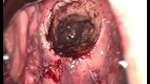

婦科leep錐切手術(shù) CIN2-3

CIN 2-3